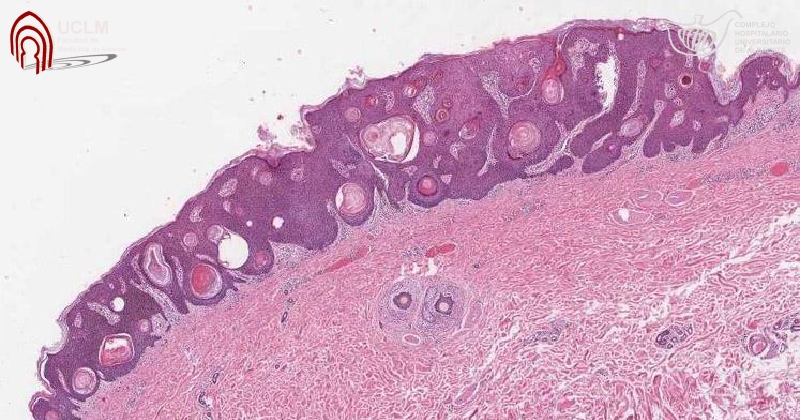

Peróxido de hidrógeno 40% (Eskata) para queratosis seborreicas

Jama , 8 de enero de 2019 La FDA ha aprobado una solución tópica de peróxido de hidrógeno al 40% (Eskata - Aclaris Therapeutics) para el tratamiento de las queratosis seborreicas elevadas (QS) en adultos. Es el primer fármaco aprobado para esta indicación. (El peróxido de hidrógeno está disponible sin receta para uso tópico como solución al 3%).